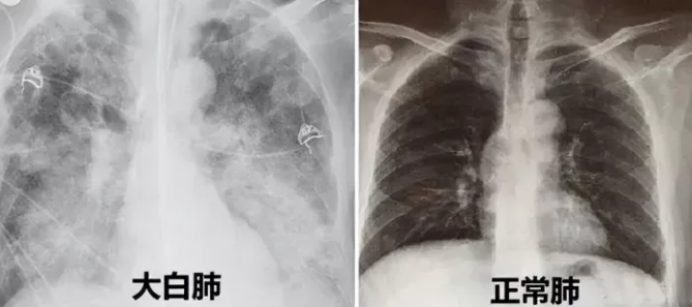

白肺是怎么来的呢?“白肺”全称为急性呼吸窘迫综合征(ARDS),一般指的是重症肺炎患者在X光或CT检查下,肺部显影呈一大片白色状而得名。

通俗来说,“白肺”,实际上是一种影像学上的描述,打个比方,一个干净的空玻璃瓶一眼看上去是通彻透明的,当玻璃瓶中装满了混浊的污水时,瓶子不再透明,看起来就是雾茫茫的一片,这就类似于“白肺”。

众所周知,肺是呼吸器官,大量的气体交换需要在肺的肺泡中完成,正常情况下肺泡中只有空气,就像是干净的玻璃瓶;当奥密克戎病毒侵犯肺泡引起炎性反应时,大量的炎性渗出液渗出到肺泡中,“玻璃瓶子”便不再透明,肺泡被液体占据无法再完成气体交换,机体就会因缺氧而引发一系列问题甚至危及生命,后果还是较为严重的,通过肺部CT检查可以清楚地显示肺部呈白茫茫的一片。